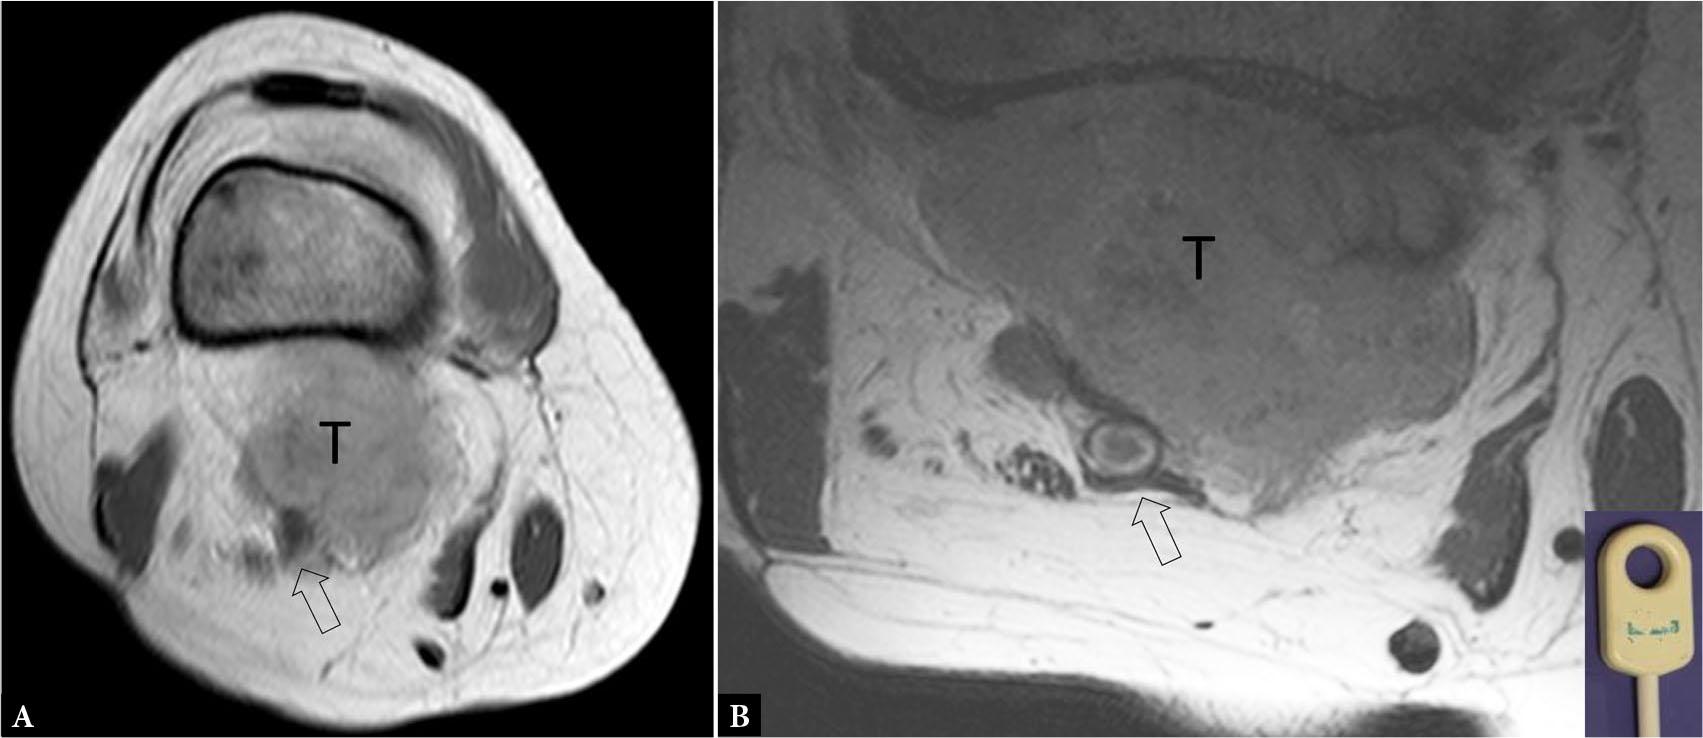

Fig. 19.

72-year-old male with biopsy-proven malignant fibrous histiocytoma of the popliteal fossa. A. PDW axial MR image with standard coil shows possible partial encasement of the popliteal artery (open arrow) by tumor (T). A, B. PDW axial MR image with microscopy coil (inset) shows the popliteal artery (open arrow), vein, and tibial nerve to be clearly separated from tumor (T)